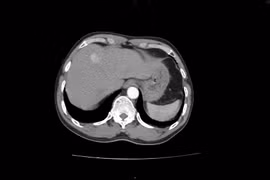

Các bác sĩ Bệnh viện Việt Nam – Thụy Điển Uông Bí vừa tiến hành phẫu thuật cắt khối u gan lớn kích thước 5x5cm cho bệnh nhân nam 70 tuổi ở Đông Triều – Quảng Ninh.

Các bác sĩ Bệnh viện Việt Nam – Thụy Điển Uông Bí vừa tiến hành phẫu thuật cắt khối u gan lớn kích thước 5x5cm, kịp thời cứu sống người bệnh nam 70 tuổi (Đông Triều – Quảng Ninh).